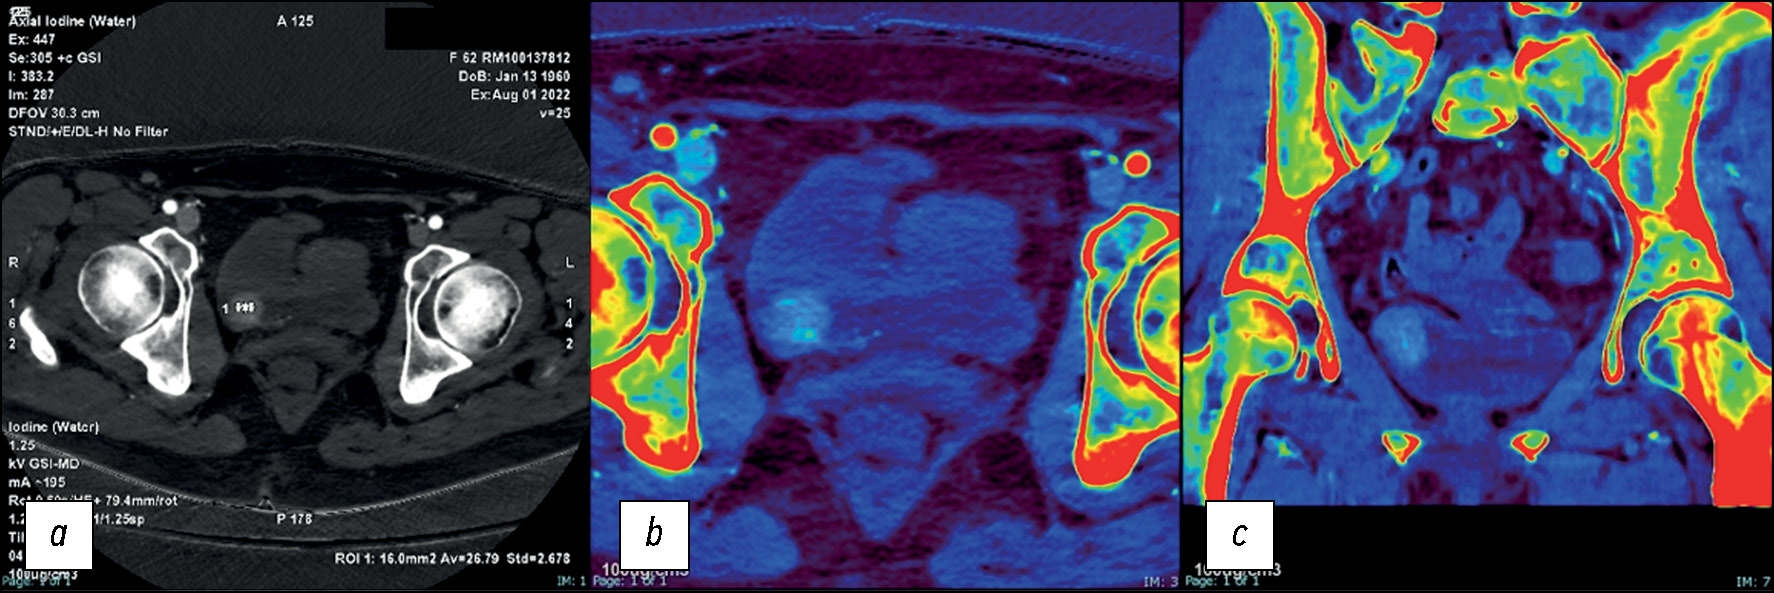

При исследовании участков поглощения йода и его отсутствия можно использовать йодные карты для определения количества йода в каждом вокселе, чтобы таким образом обнаружить небольшие участки контрастного усиления для установления характеристик очага. Йодные карты также можно использовать для разграничения сосудистых и несосудистых поражений, тоже с целью установления характеристик очага. В этом случае в нефрографической фазе количественное определение йода следует нормализовать по содержанию йода в аорте. Порог концентрации йода ≥1,0 мг/мл демонстрирует высокую чувствительность (92%) для уротелиальных опухолей. Высокая специфичность (92%) исследования может быть достигнута при пороговом значении ≥3,0 мг/мл (рис. 6–8) [42].

Рис. 6. Пациент с гематурией на фоне антикоагулянтной терапии, с подозрением на тромб: a — йодная карта в аксиальной плоскости, полученная в артериальную фазу (Av=26,79 соответствует концентрации йода в мг/мл при пороговом значении 1,3 мг/мл). Согласно данным компьютерной томографии, очаг содержит йод, поэтому есть все основания подозревать в нём новообразования мочевого пузыря; b — йодная карта с наложением цвета, полученная в артериальную фазу компьютерной томографии в аксиальной плоскости, содержание гидроксиапатита не выявлено; c — йодная карта с наложением цвета, полученная в артериальную фазу компьютерной томографии в коронарной плоскости, содержание гидроксиапатита не выявлено.